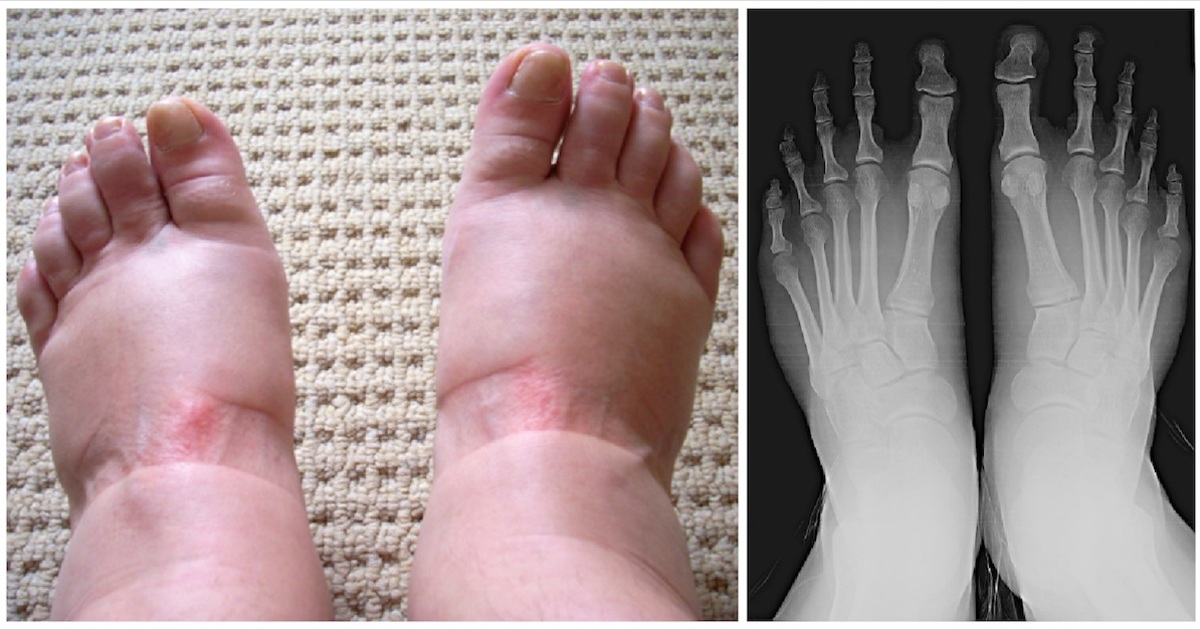

Sometimes, the swelling is related to inflammation. If your joints in your hands or feet are consistently swollen, stiff, and achy, it could point to arthritis. Rheumatoid arthritis often affects both sides of the body simultaneously, while gout famously causes a sudden, excruciatingly painful and swollen big toe. Even a simple overuse injury, like Achilles tendonitis from a new workout routine, can leave your ankles puffy and sore.